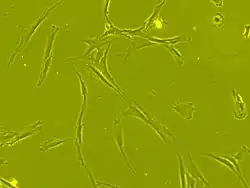

Morphologie

Les CSM ont un corps cellulaire petit, avec quelques éléments cellulaires longs et minces.

Ce corps cellulaire contient un gros noyau rond avec un nucléole proéminent, entouré de fines particules de chromatine dispersées, donnant au noyau une apparence claire.

Le reste du corps cellulaire contient une petite quantité d'appareils de Golgi, un réticulum endoplasmique rugueux, des mitochondries et des polyribosomes.

Ces cellules, longues et minces, sont largement dispersées, et la matrice extracellulaire adjacente est peuplée de quelques fibrilles réticulaires mais dépourvue d’autre types de fibrilles de collagène[39],[36].

La Société internationale de thérapie cellulaire (ISCT) a proposé des critères de définition les CSM = une cellule peut être classée MSC si elle présente des propriétés d'adhérence plastique dans des conditions de culture normales et si elle a une morphologie de type fibroblaste.